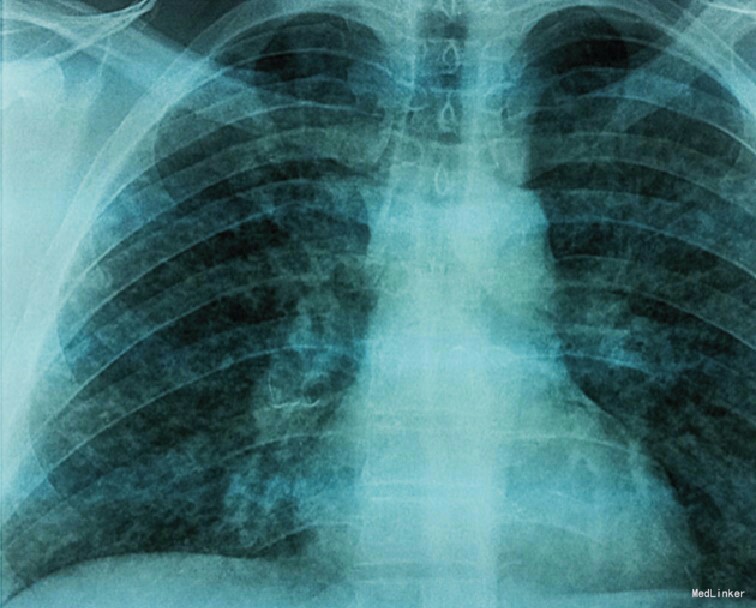

35岁青年男性,因”突然发热,呼吸困难伴胸痛、发疹性水疱”入院。患者吸烟,两个月前患者的两个儿子得水痘。既往无对该病的免疫和接触史。辅查:体温39℃,呼吸窘迫,氧饱和度88%。泛发性多形性瘙痒性皮疹、斑疹、水疱、脓疱及结痂(图1)。实验室检查提示轻度血小板减少及肝酶、乳酸脱氢酶升高。胸片提示结节性间质浸润(图2).动脉血气分析提示低氧性呼吸衰竭,PaO2为51.8 mmHg。HIV阴性。诊断:水痘肺炎;轻度肝功受损 治疗:给予支持治疗,静脉输入阿昔洛韦。随访:治疗一周后,患者完全恢复出院。 讨论:水痘肺炎是由水痘-带状疱疹病毒引起的肺炎。多发生于成年人。主要发病年龄为22-65岁。儿童少见。并发水痘肺炎者其皮疹多较一般病例广泛且严重, 密集融合的疱疹甚至遍及面部、手掌及足底, 口腔及咽部粘膜亦常被累及,皮疹呈出血性。本例患者水痘皮疹广泛。肺炎症状多数出现在发疹后的第2-6天,有在由疹前或延至疹后10 天者。体温高低不定,病情之严重程度有关;咳嗽可呈干咳或有大量痰液,约三分之一病例可有咯血;呼吸急促及紫绀较为常见,出现胸痛者约占25-50%。水痘肺炎的临床症状一般随皮疹的结痂而消失,病程1至14天不等,大多数病程在一周内转佳。胸部X线征象呈两肺弥漫性结节浸润或网织状阴影,病灶可融合呈广泛浸润灶影,常分布于肺门或肺底部。可出现两侧胸腔积液征象。病变较轻者多于1~2周内吸收,亦有延长至数月始吸收者,最后可能遗留散在的钙化灶。水痘肺炎需与继发性细菌感染所引起的支气管肺炎相鉴别。目前对水痘肺炎仅限于积极的对症及支持疗法, 一般病例无需应用激素或抗菌药便可顺利恢复,此外阿昔洛韦(无环鸟苷)治疗有一定效果。肺部严重感染特别是低氧血症并发呼吸衰竭时,除氧疗外,可作气管插管或气管切开,并加用机械呼吸治疗。糖皮质激素一般忌用,因其他原因应用激素者,如病情许可,尽量减至生理量,必要时考虑停用。若水痘病毒除肺组织外尚累及其他脏器和有并发症存在者, 预后不良。妊娠妇女罹患水痘肺炎是否影响预后尚未明确。